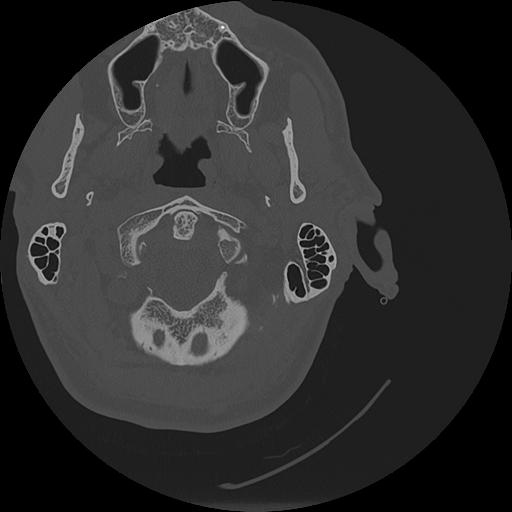

7 HUESO,,Vol,0.5,HUESO,,